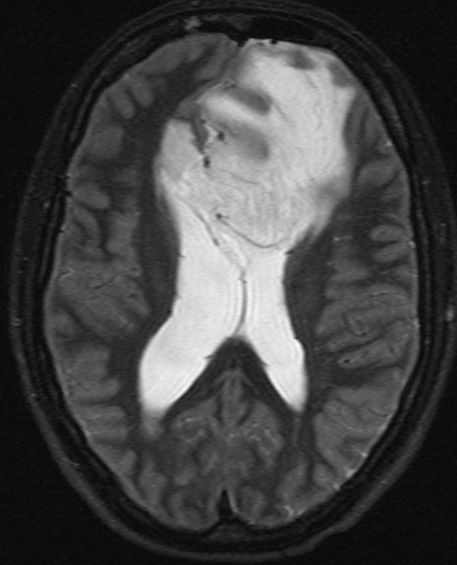

| Astrozytom II | 33jährige Frau mit einem links-frontalen Gliom Grad 2.![]()